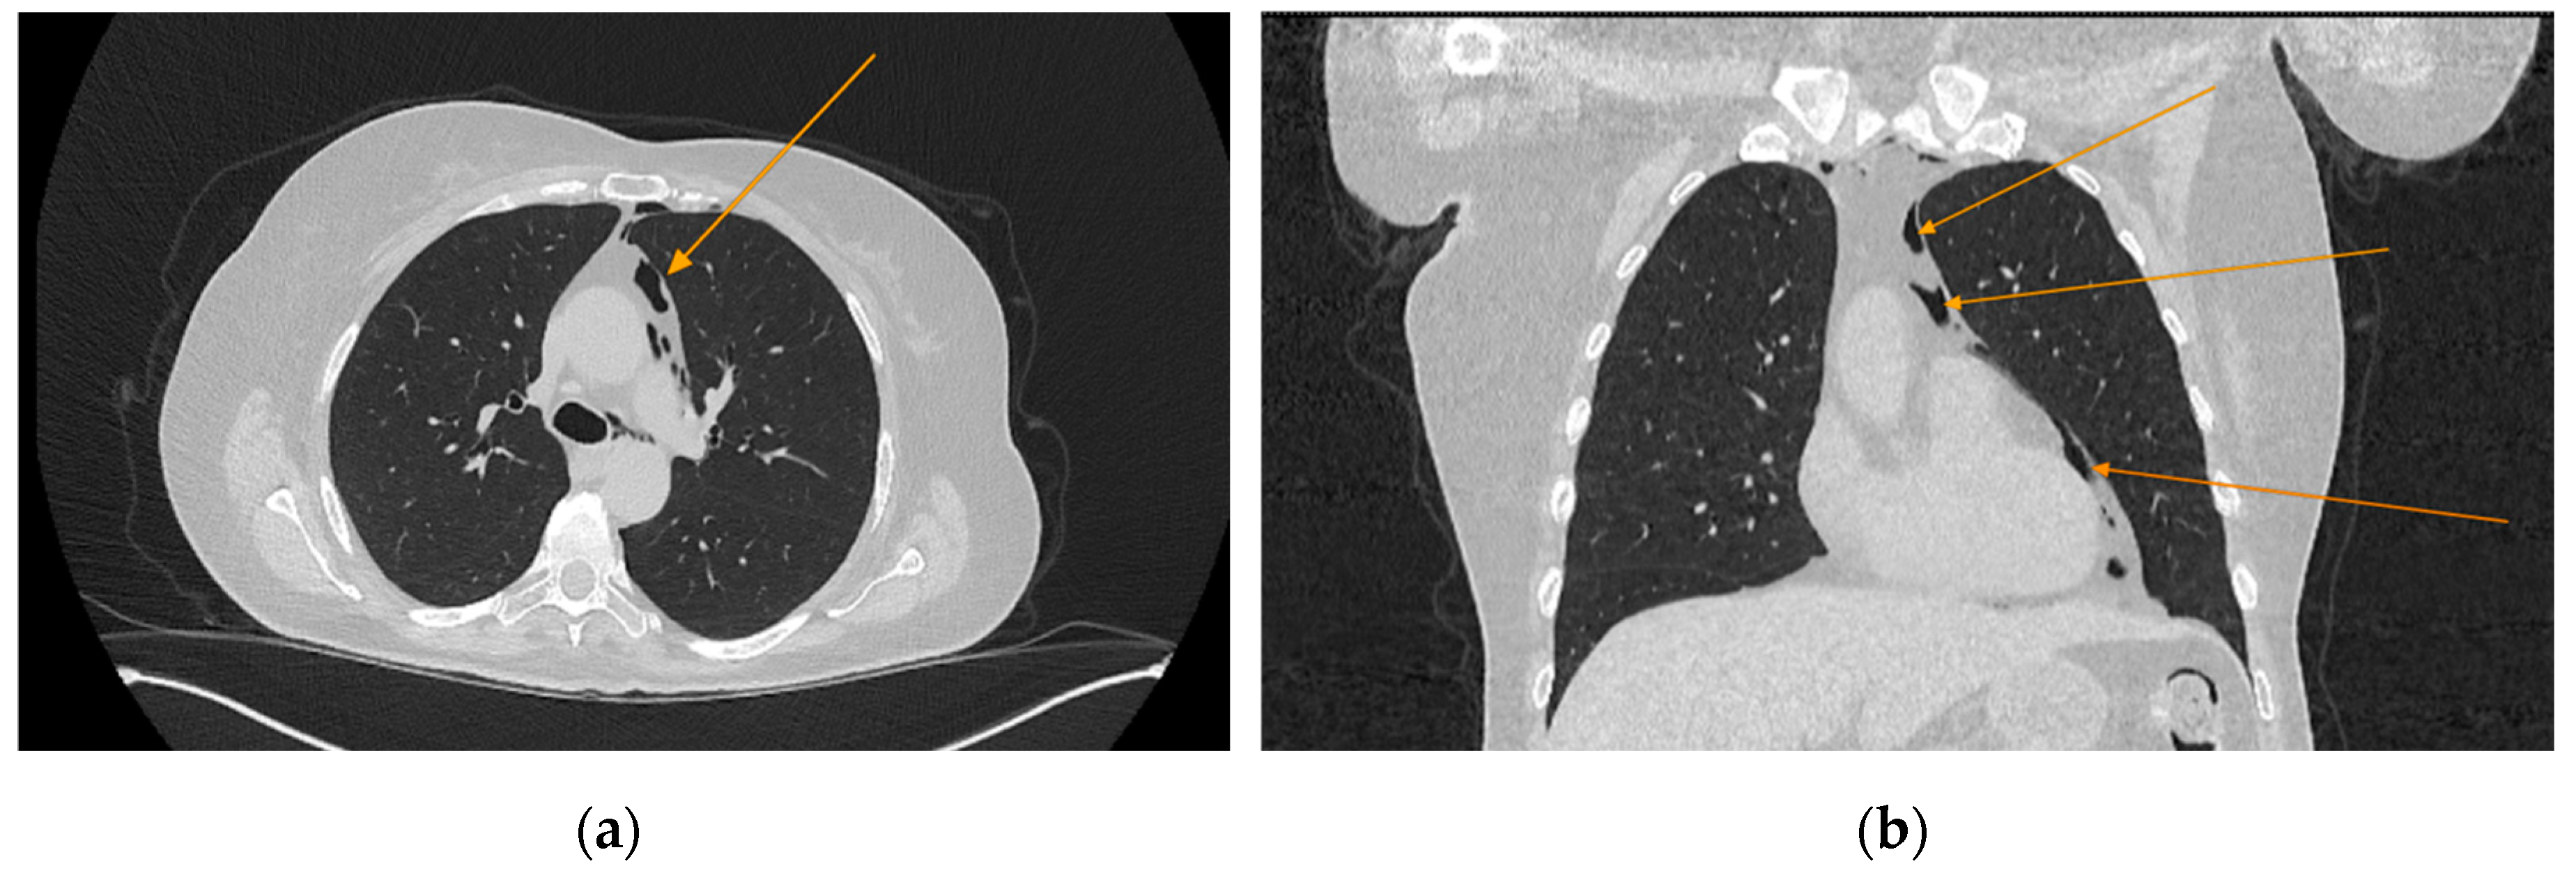

The chest CT scan performed in the emergency department (Figure 1) revealed the presence of pneumomediastinum. CT scans of the abdomen and pelvis were also performed, giving the high lipase and epigastric pain, revealing findings consistent with acute pancreatitis (with peripancreatic fluid collection, consistent with moderate acute pancreatitis per the modified CT severity index), as well as a solitary biliary stone measuring approximately 20 mm in diameter, without intra or extrahepatic biliary ducts enlargement (Figure 2).

Figure 2. Abdominal CT scan showing acute pancreatitis (arrows), axial view.

The patient was referred to diabetology in order to be admitted to hospital. Although the patient presented a good clinical and biological evolution, her condition deteriorated after about 12 hours, therefore another chest CT scan was performed, revealing extension of the pneumomediastinum in comparison to the prior scan and the presence of an additional left pneumothorax measuring approximately 7 mm (Figure 5).

Figure 5. Chest CT showing the presence of pneumothorax: (a) axial view; (b) coronal view.